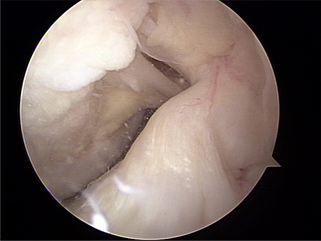

후방십자인대 파열